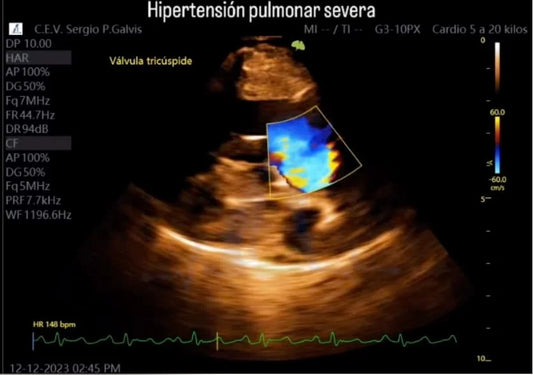

Diagnóstico y Tratamiento de la Hipertensión Pu...

La hipertensión pulmonar severa en caninos es una condición grave y frecuentemente silenciosa que aumenta la presión en las arterias pulmonares, afectando la respiración y el funcionamiento del corazón. Sus...